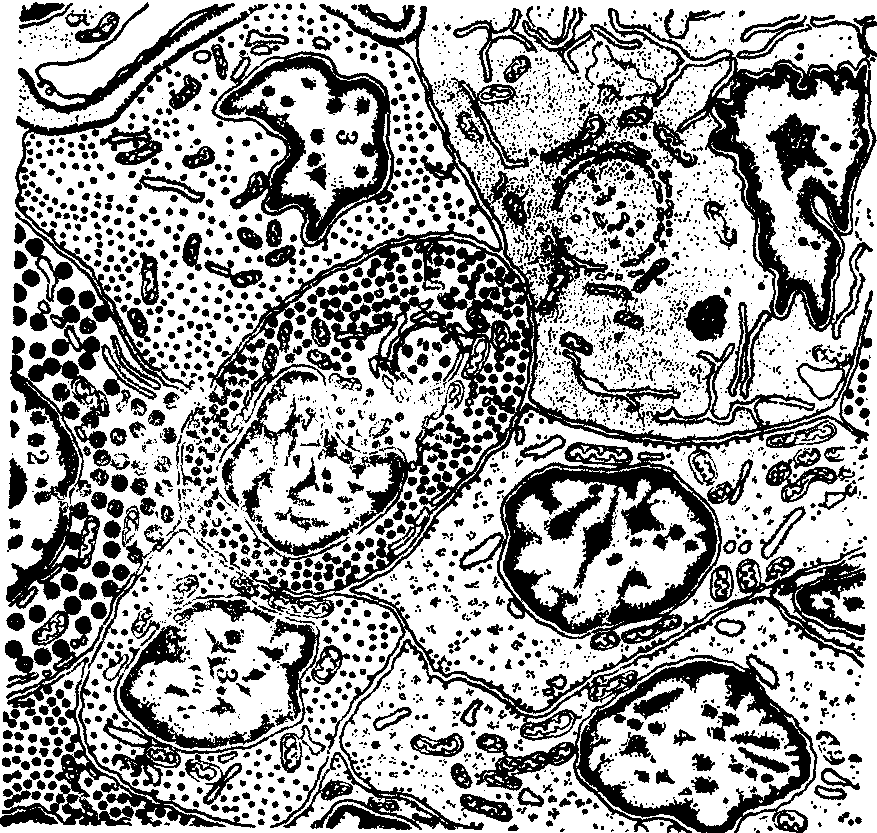

(1)远侧部: 此部最大,占腺总体积的75%(彩图4)。腺细胞集合成团或索。有些细胞组成滤泡。细胞团和索间充满丰富的窦状毛细血管。结缔组织除伴随较大的血管外,只有少量网状纤维围绕腺细胞和毛细血管。依胞质着色性质不同,腺细胞分嗜色细胞和嫌色细胞。根据胞质颗粒着色的特点,嗜色细胞又分嗜酸细胞和嗜碱细胞。但一般用以显示腺细胞的染料都是酸性染料,故“嗜酸”和“嗜碱”之称并不反映细胞内物质的酸碱性。人的三种细胞比例因个体和生理状况差异很大,嫌色细胞约占50%,嗜酸细胞35%,嗜碱细胞15%。曾以几种特殊染色法用于区分人和哺乳类腺细胞类型,但因观察种属和所用染色法的差别,对各种细胞的命名不一;有的用希腊字母命名,有的用被着色的染料命名,以致细胞名称较混乱。近年应用电镜和免疫细胞化学法对腺细胞的深入研究,趋于按细胞所产生的激素对每种细胞定名。

嗜酸细胞轮廓清楚,比嫌色细胞大,圆或卵圆形,直径14~19μm(彩图4)。高尔基复合体发达,有许多小杆状线粒体。胞质内满含分泌颗粒,易被伊红和桔黄G等染色。根据染色性质和颗粒形态,将细胞分二种。一种是促生长激素细胞,又名α细胞,数目较多,常聚集成群,分布于前叶后外侧部。粗面内质网丰富,高尔基复合体明显。有许多致密圆形颗粒,直径350~400nm(图2),分泌促生长激素。儿童患脑垂体嗜酸细胞瘤,可致巨人症;成人患此瘤时,致肢端肥大症。儿童缺少此种激素,则致侏儒症。此激素为蛋白质,对蛋白质、脂类和碳水化物的代谢起显著作用。它对骺软骨有特殊的刺激生长作用,影响人体的生长。另一种是催乳激素细胞,也名ε细胞,数目较少,多分散存在。颗粒形状不规则,直径约600nm(图2)。在不授乳的雌性动物,粗面内质网不多,高尔基复合体小。受孕和授乳期时细胞数目增多并变大。高尔基复合体发达,粗面内质网丰富,有中等数量的溶酶体。免疫细胞化学法证明,此种细胞分泌催乳激素。断乳时溶酶体增多,分解过剩的分泌颗粒和粗面内质网。肥大的细胞渐趋于不活跃状态。催乳激素为蛋白质,它促使和维持乳腺分泌; 在啮齿类也维持黄体的分泌功能。人患催乳细胞瘤时,虽未妊娠和授乳,也分泌大量乳汁。

图2 腺垂体细胞超微结构模式图

1.促生长激素细胞 2.催乳激素细胞 3.促性腺激素细胞 4.促甲状腺激素细胞 5.毛细血管

嗜碱细胞不易被苏木精染色,在普通染色切片中不易辨认,但易被安尼林蓝染色,PAS反应阳性。它们比嗜酸细胞大,卵圆或多角形,多分布于前叶的中心和前部(彩图4),可分三种:

❶促甲状腺激素细胞:又称β2细胞,较大,呈多角形,常成群。胞质含许多小而致密的分泌颗粒,直径100~150nm,位于胞质外周部(图2)。动物实验表明,切除甲状腺可使此种细胞增多和肥大;注射甲状腺素,可致它们萎缩。免疫细胞化学法已定位促甲状腺激素于此种细胞。此激素为糖蛋白,它维持甲状腺滤泡上皮细胞的构造和分泌功能;

❷促性腺激素细胞: 即δ细胞,为圆形,大小不等,单个散在于细胞索中。胞质中高尔基复合体明显,粗面内质网较多,有许多致密的分泌颗粒,直径约150~250nm(图2)。它们分泌卵泡刺激素和黄体生成素,两者都是糖蛋白。但由一种细胞产生两种激素,还是两种细胞各产生一种激素,还未确知。卵泡刺激素促使卵巢的卵泡生长和卵泡细胞分泌雌激素,并在黄体生成素的协同作用下,使卵泡成熟、排卵和形成黄体。它还促进睾丸生精小管细胞分裂和生成精子。黄体生成素也名间质细胞刺激素。它在卵泡刺激素的作用基础上,促使排卵的卵泡形成黄体和维持黄体的分泌功能; 它还促进睾丸间质细胞分泌睾酮;

❸促肾上腺皮质激素细胞:为卵圆形或星形,有的有突起,多分布于远侧部中心偏前,也见于结节部和中间部。胞质密度低,粗面内质网少,分泌颗粒少,直径200nm,常集中于胞质外周部。切除动物的肾上腺皮质可致细胞变大和增多,并含较多的分泌颗粒。免疫细胞化学法已表明此种细胞分泌促肾上腺皮质激素,并显示此种细胞和中间部的一些细胞可能分泌促黑色素细胞刺激素。这二种激素是由一种还是两种细胞产生,还不清楚。对于此种细胞是属于嗜碱细胞还是嫌色细胞,也有不同意见。

嫌色细胞呈小圆形或多角形,胞质少、着色淡,细胞界限不清。光镜下未见胞质含分泌颗粒(彩图4)。它们常成群位于细胞团中。先前认为它们是未分化的贮备细胞。电镜研究见远侧部只有少数细胞不含分泌颗粒,比光镜所见的少得多。现认为光镜下所见的嫌色细胞,多数是脱颗粒的嗜酸和嗜碱细胞。嗜酸和嗜碱细胞的分泌活动是周期性的,细胞释放激素后,胞质只有少数分泌颗粒或不含颗粒。各种细胞很少见有丝分裂和退化。如确有未分化的细胞,也只占少数。